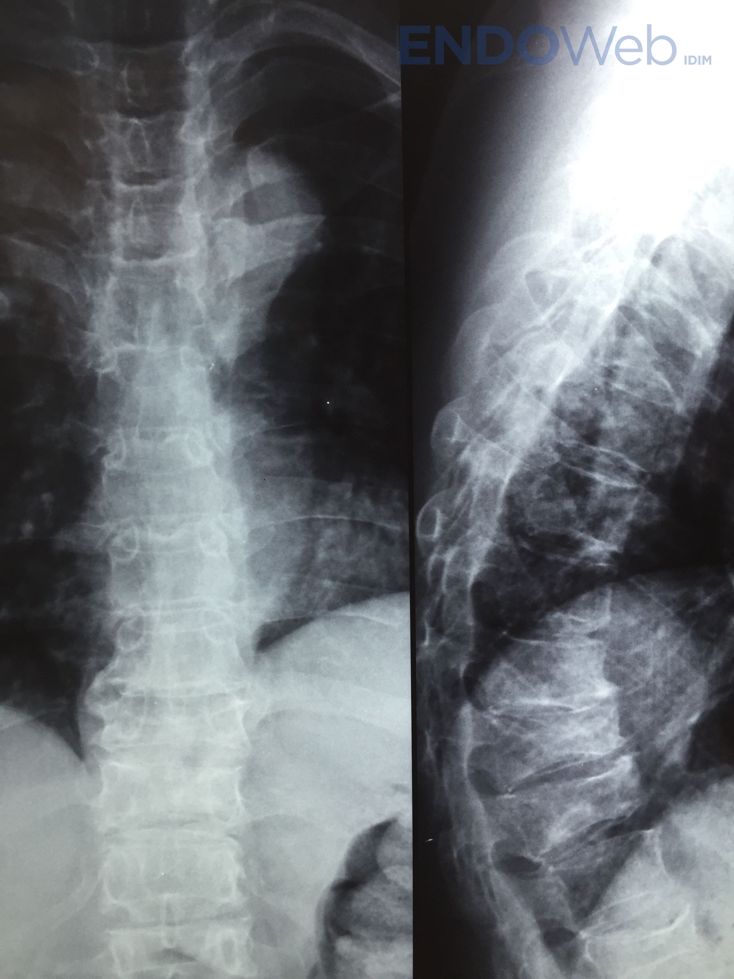

Se solicitó radiografía de columna dorso-lumbar:

Disminución altura vertebral cuerpos vertebras dorsales: D5, D8, D10 y D11. Biconcavidad vértebras lumbares L1 L2 L3